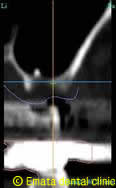

CT検査の結果、一部分が上顎洞と間に骨がないことががわかりました。上顎洞の炎症は見受けられません。

CT像